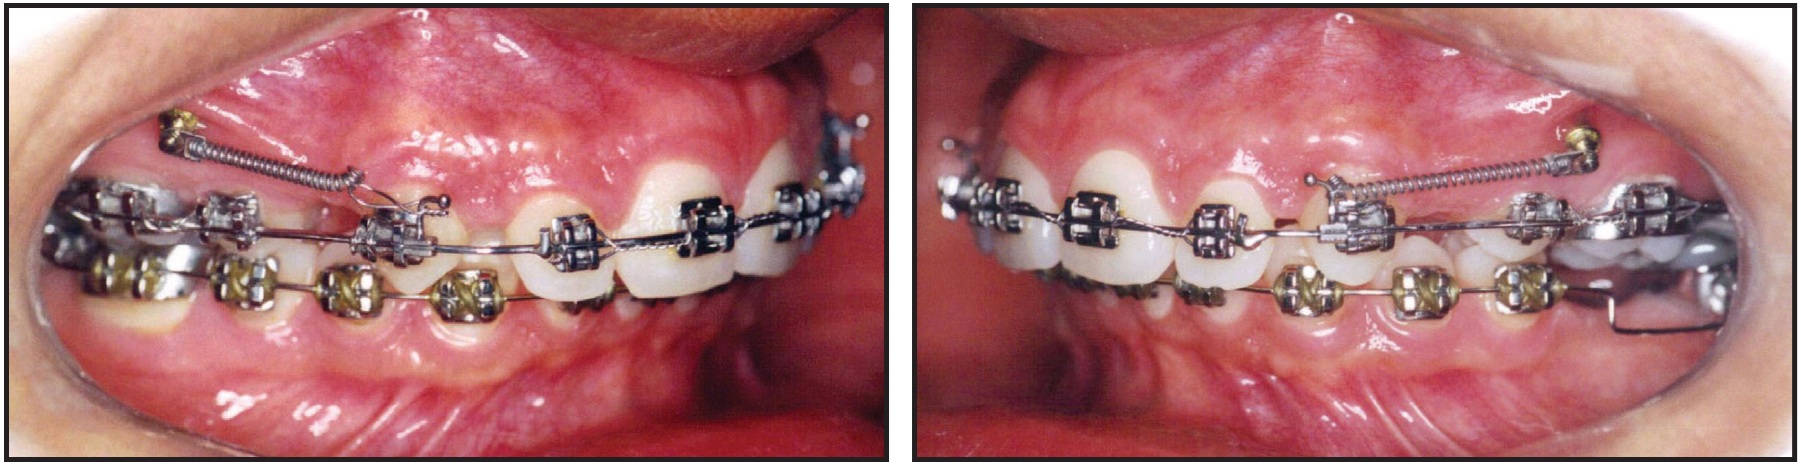

After nine months of treatment, the miniscrews*** were inserted, and the patient was referred for extraction of the first premolars. One week after the extractions, 100g nickel titanium closed-coil springs† were attached between the miniscrews and a crimpable hook positioned mesial to the canine brackets to move these teeth independently (Fig. 3).

Fig. 3 Maxillary canine retraction with miniscrew anchorage.

Four weeks later, once the upper canines were in a Class I relationship, an .019" x .025" closing-loop archwire with Bull loops distal to the lateral incisors was placed for incisor retraction (Fig. 4).

Fig. 4 Closing-loop archwire used for maxillary incisor retraction.